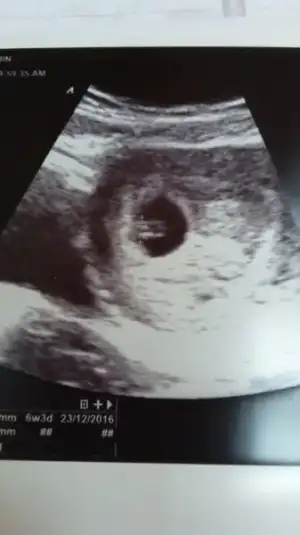

Kzilarr banada. Yorum yaparmisinizzz lutfen

• IMG-20160502-WA0006.webp

IMG-20160502-WA0006.webp

11,5 KB · Görüntüleme: 83